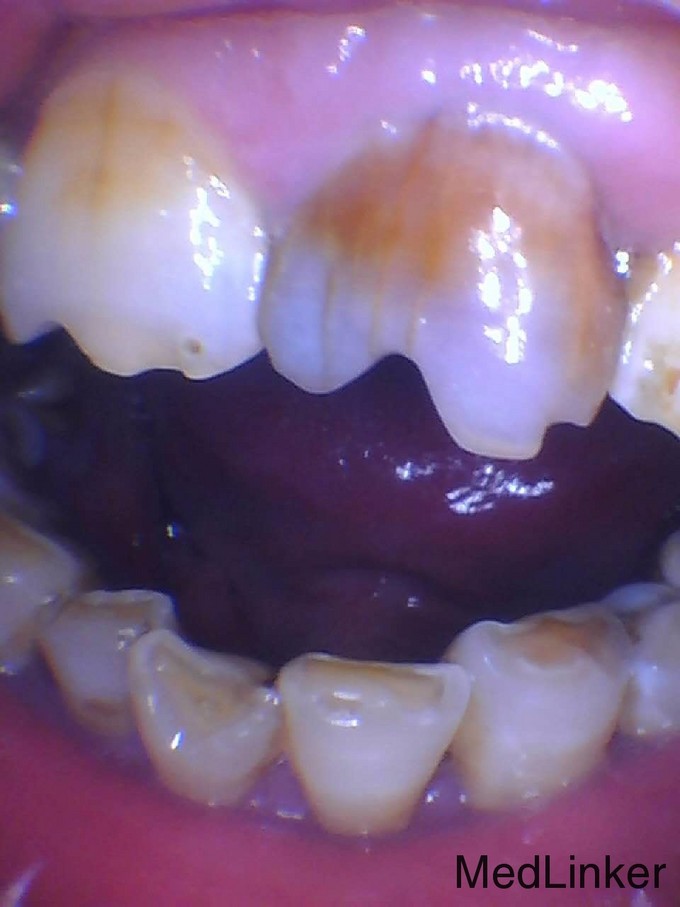

右上前牙曾治疗过,颜色黑,要求治疗

前牙变色美学修复

变色牙的美学修复